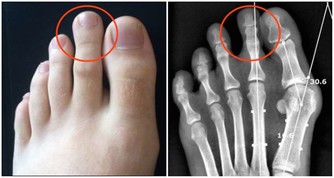

1、關節殘疾

體內的尿酸升高,超出人體承受的範圍,尿酸會形成結晶沉積在關節、皮膚、血管等地方,容易出現炎症。

痛風反復發作導致慢性痛風性關節炎,又會導致發作更加頻繁,間歇期縮短。疼痛逐漸加劇,受累的關節以膝、踝、肘關節多見,嚴重者可累及肩、髖、脊柱,很容易誘發關節的破壞與畸形,導致關節殘疾。

4、痛風石

痛風石的形成是長期高尿酸血症引起的組織損傷的結果,是痛風的特徵性病變;沉積在關節囊,影響關節活動;可導致骨“鑿孔”樣損害,嚴重者可導致骨折。關節脫位及畸形;痛風石破潰後,不易癒合,極易導致截肢悲劇。